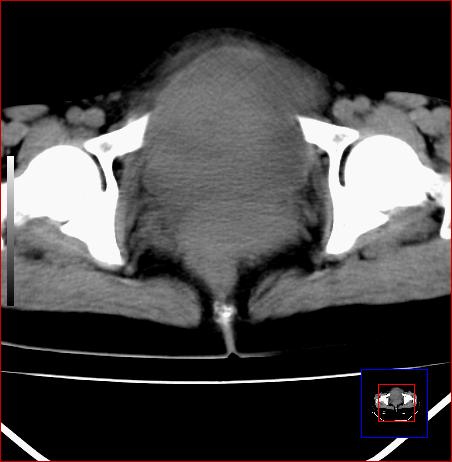

标题: CT15141:子宫肌瘤还是卵巢肿瘤 [打印本页]

腹部包块1年余,近两月明显增大,月经量多

病灶呈实性包块,边界清晰,似与子宫分界不清,考虑:子宫肌瘤

病灶呈实性包块,边界清晰,似与子宫分界不清,密度低于肌肉,考虑:恶性可能,确诊需要妇科诊刮。

源于子宫的肿瘤,性质待定。恶性可能性大。